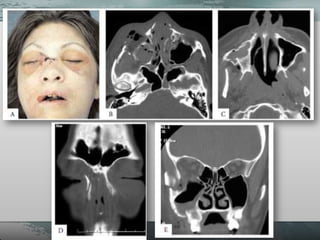

• São causadaspor impactos graves, diretos e rombos no terço médio da face. • Deslocamento ósseo geralmente se dá devido a direção da força traumática. • Podem ser as mais letais.

• 27.

• Retrusão doterço médio da face. • Má-oclusão, mordida aberta com contato prematuro dos molares e deslocamento posterior da maxila. • Laceração dos tecidos moles do vestíbulo ou do palato. • Epistaxe, hematoma periorbitário, equimose subconjuntival.

• 28.

• Dish-face: fraturascom deslocamento onde a face fica côncava e o terço médio alongado. • Extravasamento do líquido cefalorraquidiano (também denominado como fluído cerebroespinhal) pelo nariz (rinoliquorréia) ou ouvidos (otoliquorréia). – Fratura basilar de crânio.

• É umafratura que classicamente tangencia a margem inferior da abertura piriforme e se dirige horizontalmente através da parede anterior do seio maxilar, bilateralmente, até a tuberosidade, com disjunção pterigomaxilar. • Características clínicas: – Mobilidade da porção alveolar da maxila, edema, equimose periorbital, dor, mudança na oclusão por intrusão ou giroversão da maxila.

• Caracterizada porlinhas de fratura que se iniciam na região nasofrontal, é consequência de impacto anterior muitas vezes comprometendo as estruturas do nariz e septo nasal. • Características clínicas: – Mobilidade da maxila, incluindo a pirâmide nasal, edema e equimose periorbital, dor, rinorréia.

• Nestes casosa linha de fratura se estende através da sutura naso-frontal às paredes mediais e assoalho da órbita alcançando as suturas zigomático-frontais e arco zigomático. • Dá ao paciente um aspecto de face alongada (cara de cavalo).